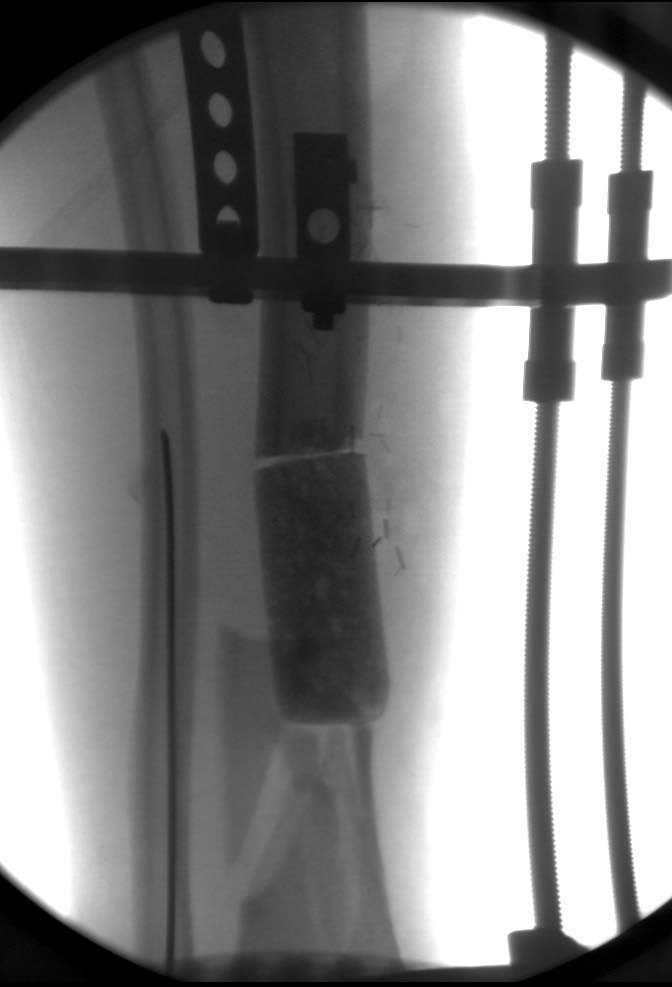

Здравствуйте уважаемые коллеги, прошу поделиться опытом лечения подобных повреждений-осложнений. Пациент Б. 40 лет, поступил в клинику 6.11.19 с огнестрельным переломом н/3 правого бедра и повреждением магистральных сосудов. Произведена ПХО ран, стабилизация перелома(с укорочением на 5 см.)стержневым АВФ, шов сосудов конец в конец. К сожалению, неверная выжидательная тактика привела к нагноению раны(Kl.pneumoniae).22.11.19 Этапная ХО раны, перемонтаж АВФ по типу-гибрид, удаление девитализированных костных фрагментов, депонирование дефекта бусами-спейсерами (амикацин-ванкомицин),VAC, Тигацил 100 мг.сут.26.11, 29.11, 3.12-этапные ХО с заменой бус и VAC,бак.посевы(возбудитель присутствует) . Макроскопически рана очистилась, гранулирует, однако имеется воспаление вокруг стержней. t. тела-в пределах нормы, лейкоциты снизились с 9,5 до 6.3, СОЭ с 62 до 31,СРБ с 98 до 49,гемогробин-98.Какую тактику применить на данном этапе?1 Masquelet с конверсией на гвоздь(пластину) с антибиотиком.2Аппаратное лечение с транспортом кости.3Другие возможные варианты.Заранее благодарю за помощь.

Теперь по поводу данного случая - “спейсер” из цемента предупреждает инфекцию и сохраняет пространство. Но вместо “бус” “цилиндрическая форма” более удобная, вокруг нее образуется ровная трубчатая поверхность “псевдо-мембраны” что в дальнейшей позволит закрыть небольшие дефекты “графтом” или во время удлинения облегчает скольжение регенерата как по трубке.

Данный случай не огнестрельная рана, а результат мотоциклетной аварии. Независимо от повреждения при таких обширных дефектах мягких и костной тканей применяется схожая тактика. Как видно, после нескольких I&D для создания “pseudo membrane” применили цилиндрический блок из цемента. Дефект мягких тканей закрыли свободным Anterior Thigh Graft. Из малого доступа цилиндр удален небольшими кусочками, а пространство заполнили бусами для освобождения пространства. По мере приближения регенерата освободили пространство удалением бус через небольшой разрез. Этап созревание регенерата можно было ускорить усилением интрамедуллярным гвоздем, но решили закончить методом Илизарова.